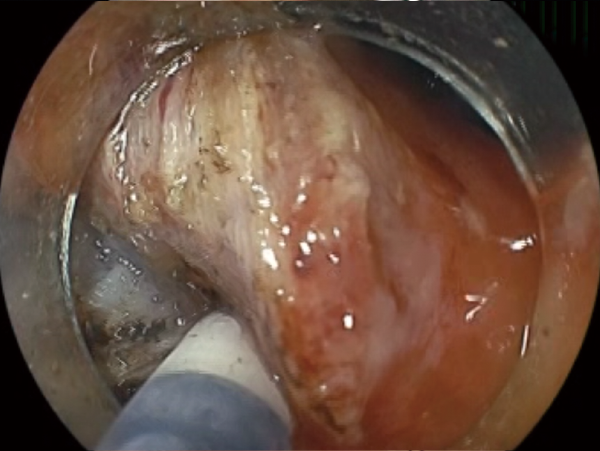

Able to arrest small amounts of bleeding during dissection without replacing the knife.